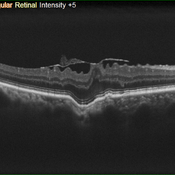

Focal Choroidal Excavation and Epiretinal Membrane

Jun 27 2019 by Andre Beckenkamp

56 y.o. male complaining of blurred vision.

Photographer: Andre Beckenkamp

Imaging device: Nidek RS 3000

Condition/keywords: choroidal excavation, epiretinal membrane (ERM)